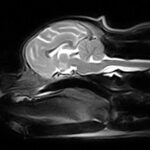

Risonanza Magnetica

Nella nostra Clinica Veterinaria è possibile effettuare la Risonanza Magnetica

Vuoi sapere come funziona una Risonanza Magnetica?? leggi l’articolo

Che differenza c’è tra TAC e Risonanza Magnetica?? leggi l’articolo